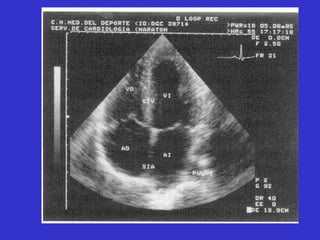

Adaptaciones cardiacas al ejercicio Hallazgos clínicos Aumento del volumen de todas las cavidades Ligero engrosamiento uniforme de las paredes Ligero aumento de la masa ventricular izq.    relación capilares/miofibrillas y circ.colateral Indice de contractilidad normal Mejora capacidad llenado ventricular ECOCARDIOGRAFÍA “ LOS DEPORTES AERÓBICOS SON LOS QUE PRODUCEN UN MAYOR AUMENTO DE LAS DIMENSIONES DEL V.I. Y DEL GROSOR DE LAS PAREDES”

Adaptaciones cardiacas alejercicio Hallazgos clínicos Aumento del volumen de todas las cavidades Ligero engrosamiento uniforme de las paredes Ligero aumento de la masa ventricular izq.  relación capilares/miofibrillas y circ.colateral Indice de contractilidad normal Mejora capacidad llenado ventricular ECOCARDIOGRAFÍA “ LOS DEPORTES AERÓBICOS SON LOS QUE PRODUCEN UN MAYOR AUMENTO DE LAS DIMENSIONES DEL V.I. Y DEL GROSOR DE LAS PAREDES”

• #157 Figura 11.10 Nuestro Imagen bidimensional obtenida en la ecocardiografía realizada desde una proyección de 4 cámaras apical.